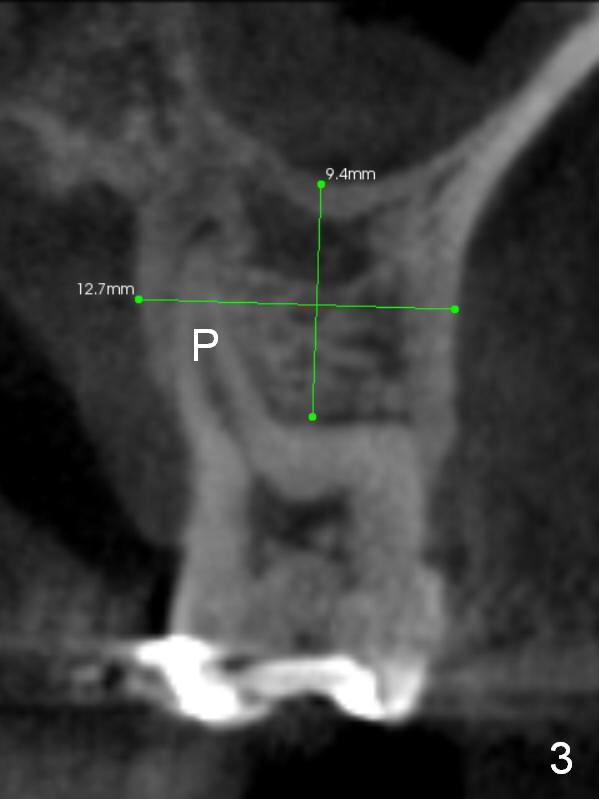

A 48-year-old lady has 4 relative contraindications to immediate implant: 1. infection is so severe at the site of #14 (the posterior maxilla with low bone density, Fig.4,5) that there is no enough bone to support the implant (Fig.7 illustration (1, 2); 2. dental insurance runs out; 3. she shows late in the afternoon when there is not enough staff; 4. she has had 2 immediate implants placed (Fig.4: #15 (3,4)). After socket preservation (Fig.8,9), she is most likely to return for implant placement.

It is noteworthy that the tooth #14 was less affected than #15 22 months earlier (Fig.1 (CBCT sagittal section), 2 (axial), 3 (coronal)). Calculus on the surface of the palatal root (Fig.6 P) is associated with the palatal abscess (Fig.5 P). S: septum.